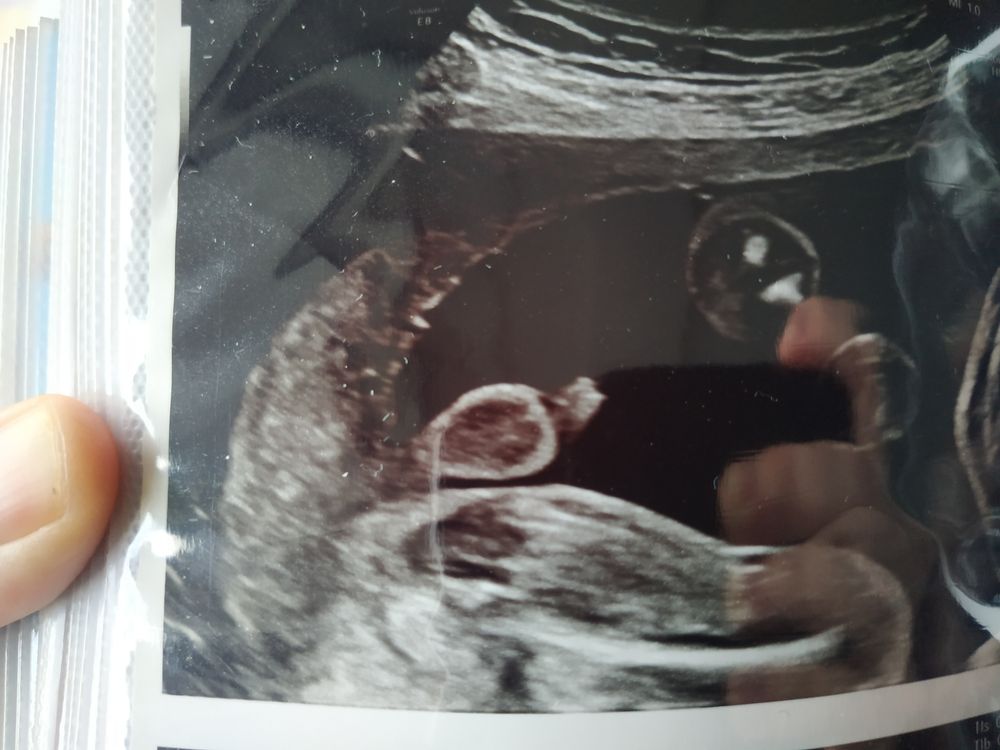

Я такое видела у младшего сына. Мошонка и два яичка в нём. Правда чётче было. По мне так очевидные яички.

На нижнем еще и писюн как будто, кругляшок такой

На последнем, 34 недели, вообще хрен пойми, где что